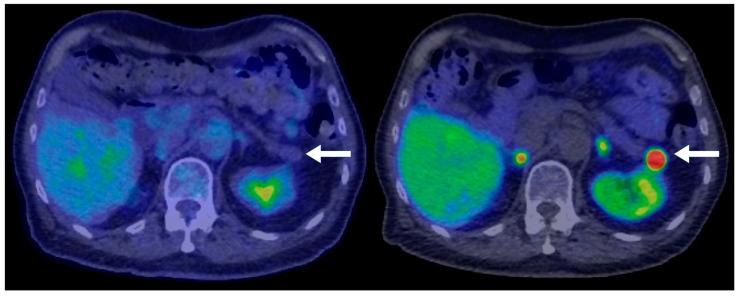

Pancreatic neuroendocrine neoplasms (PNENs) are rare but clinically significant tumors with variable radiological presentations that complicate diagnosis. While typical PNENs are well characterized, atypical features, such as cystic or hypoenhancing patterns, are less understood and can lead to diagnostic delays or misdiagnosis. This study aimed to evaluate atypical radiological presentations of PNENs, focusing on their impact on diagnostic pathways and differentiation from other pancreatic pathologies. A retrospective review was conducted of all PNEN cases diagnosed at a single tertiary center between 2010 and 2020. Cases with histopathological confirmation and available cross-sectional imaging were included. Radiological features were categorized as typical (solid and hyperenhancing) or atypical (cystic and hypoenhancing). Demographic, radiological, and pathological data were analyzed. Comparisons between typical and atypical PNENs were performed using descriptive and inferential statistics. Among 77 PNEN cases, 39 met the inclusion criteria. Atypical radiological presentations were identified in 46% of cases, including cystic (18%) and hypoenhancing (28%) lesions. Hypoenhancing PNENs were significantly more likely to present with advanced disease (54% vs. 14% in typical PNENs, = 0.016). In contrast, none of the cystic PNENs exhibited advanced disease. Atypical PNENs posed greater diagnostic challenges, with alternative diagnoses initially considered in 64% of hypoenhancing and 43% of cystic cases compared to 10% of typical PNENs ( = 0.0042). Atypical PNENs, particularly hypoenhancing lesions, present significant diagnostic challenges and are more likely to be associated with advanced disease. These findings highlight the need for improved recognition of atypical imaging patterns and more precise diagnostic strategies. However, the retrospective design and small cohort size limit the generalizability of our findings. Further multicenter studies are warranted to refine the imaging criteria and optimize the differentiation from other pancreatic neoplasms.

胰腺神经内分泌肿瘤(PNENs)虽罕见,但具有临床意义,其放射学表现多样,使诊断变得复杂。典型的PNENs特征明确,但非典型特征,如囊性或强化减弱模式,了解较少,可能导致诊断延迟或误诊。本研究旨在评估PNENs的非典型放射学表现,重点关注其对诊断途径的影响以及与其他胰腺病变的鉴别。对2010年至2020年在单个三级中心诊断的所有PNEN病例进行了回顾性研究。纳入有组织病理学证实且有横断面影像资料的病例。放射学特征分为典型(实性且强化明显)或非典型(囊性且强化减弱)。对人口统计学、放射学和病理学数据进行分析。使用描述性和推断性统计对典型和非典型PNENs进行比较。在77例PNEN病例中,39例符合纳入标准。46%的病例发现有非典型放射学表现,包括囊性病变(18%)和强化减弱病变(%)。强化减弱的PNENs出现晚期疾病的可能性显著更高(54%,而典型PNENs为14%,P = 0.016)。相比之下,囊性PNENs均未出现晚期疾病。非典型PNENs带来更大的诊断挑战,与典型PNENs的10%相比,64%的强化减弱病例和43%的囊性病例最初考虑了其他诊断(P = 0.0042)。非典型PNENs,尤其是强化减弱病变,带来显著的诊断挑战,且更可能与晚期疾病相关。这些发现凸显了提高对非典型影像模式的认识以及采用更精确诊断策略的必要性。然而,回顾性设计和小样本队列限制了我们研究结果的普遍性。有必要进行进一步的多中心研究以完善影像标准并优化与其他胰腺肿瘤的鉴别。